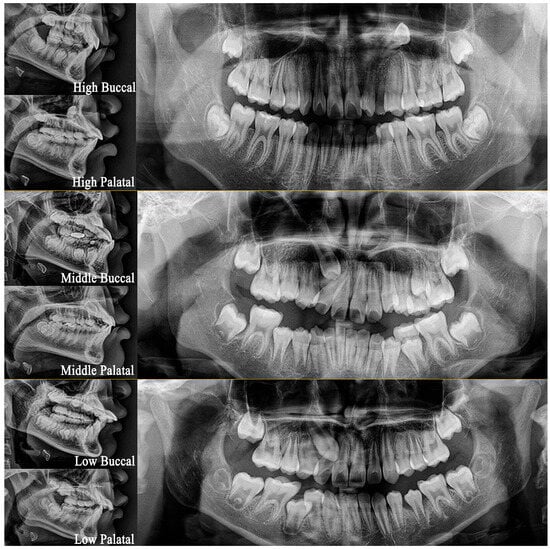

| Case Number | Impacted Canine Position | Adjacent Tooth Root Resorption | ||

|---|---|---|---|---|

| Height | Antero-Posterior | Vertical/Horizontal | ||

| 1 | High | Buccal | Horizontal | Yes (MD) |

| 2 | High | Buccal | Vertical | No |

| 3 | High | Buccal | Horizontal | Yes (MD) |

| 4 | High | Palatal | Vertical | Yes (AP) |

| 5 | High | Palatal | Horizontal | No |

| 6 | Middle | Buccal | Horizontal | No |

| 7 | Middle | Palatal | Horizontal | No |

| 8 | Low | Buccal | Vertical | Yes (AP) |

| 9 | Low | Buccal | Horizontal | Yes (AP) |

| 10 | Low | Palatal | Vertical | Yes (MD) |